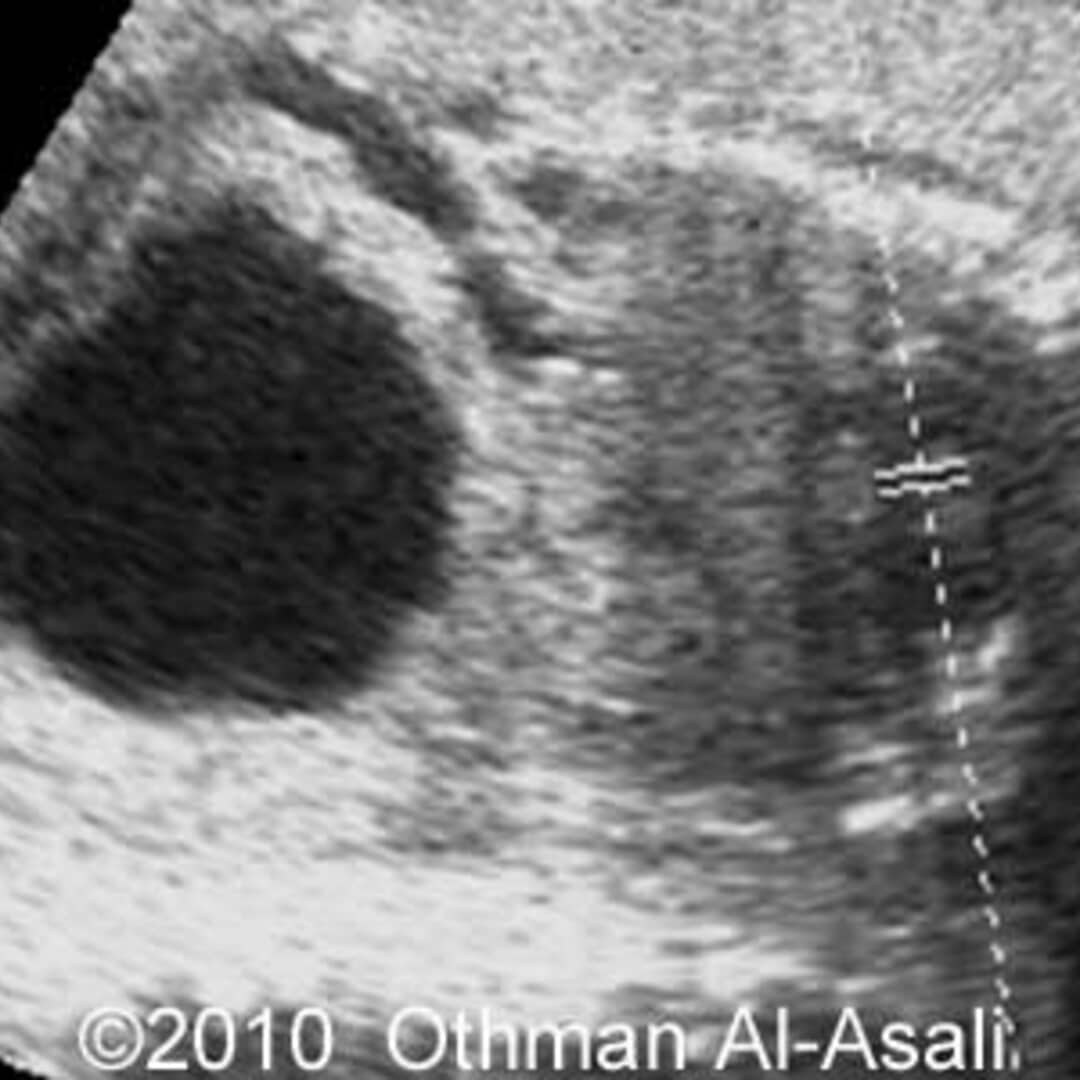

Keyhole Sign In Posterior Urethral Valve . Ultrasound examination shows a dilated, thick. bernardes ls, aksnes g, saada j, masse v, elie c, dumez y, et al. the most common cause of fetal bladder outlet obstruction is posterior urethral valves. keyhole sign in posterior urethral valve. ultrasound plays an important role in characterizing this condition, revealing a classic configuration known as. It refers to the appearance of the proximal. posterior urethral valves are a rare congenital disorder affecting the male urinary tract, characterized by abnormal membranous folds in the. the keyhole sign is an ultrasonographic sign seen in boys with posterior urethral valves. How specific is it for the diagnosis of posterior. Hydronephrosis in a male fetus can be an indicator for several different possible diagnoses, including posterior urethral valves.